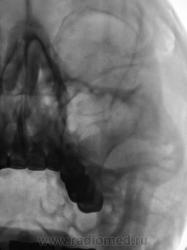

Случай 2.

Пациент направлен оториноларингологом на рентгенографию придаточных полостей носа.

в левой гайморовой пазухе отек слизистой, в альвеолярной бухте просится пломбировочный материал. хорошо бы панорамную томографию или дентальный снимок, или гайморография в прямой и левой боковой проекциях

А ведь пожалуй Вы правы! особенно по поводу пломбировочного материала. Что скажет автор случая по поводу анамнеза? Если таковой можно "догнать"?